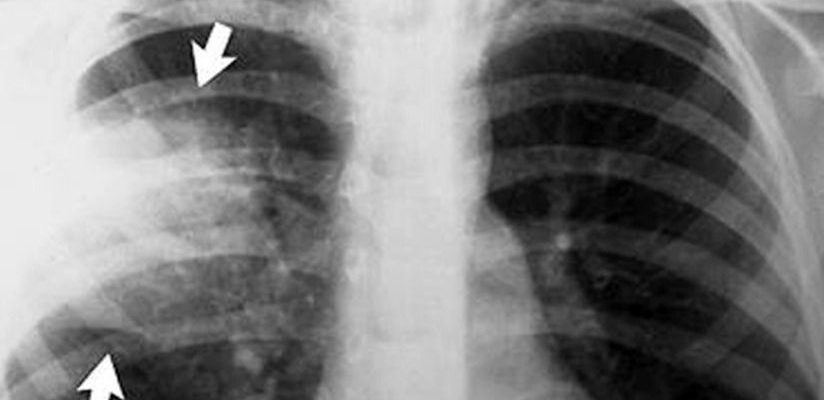

Рентген снимок атипичной пневмонии

Патологический процесс можно диагностировать с помощью рентгена. Таким образом, форма микоплазмы характеризуется гетерогенной инфильтрацией легочной ткани и может быть плохо выраженной или умеренной интенсивности.

При легионеллезе на снимке видны круглые инфильтраты, расположенные на поверхности одной доли легкого. В некоторых случаях инфильтраты сливаются.

Плеврит присутствует у 25% пациентов одновременно с пневмонией с небольшим скоплением секрета в плевральной полости.

Правосторонняя бронхолегочная пневмония